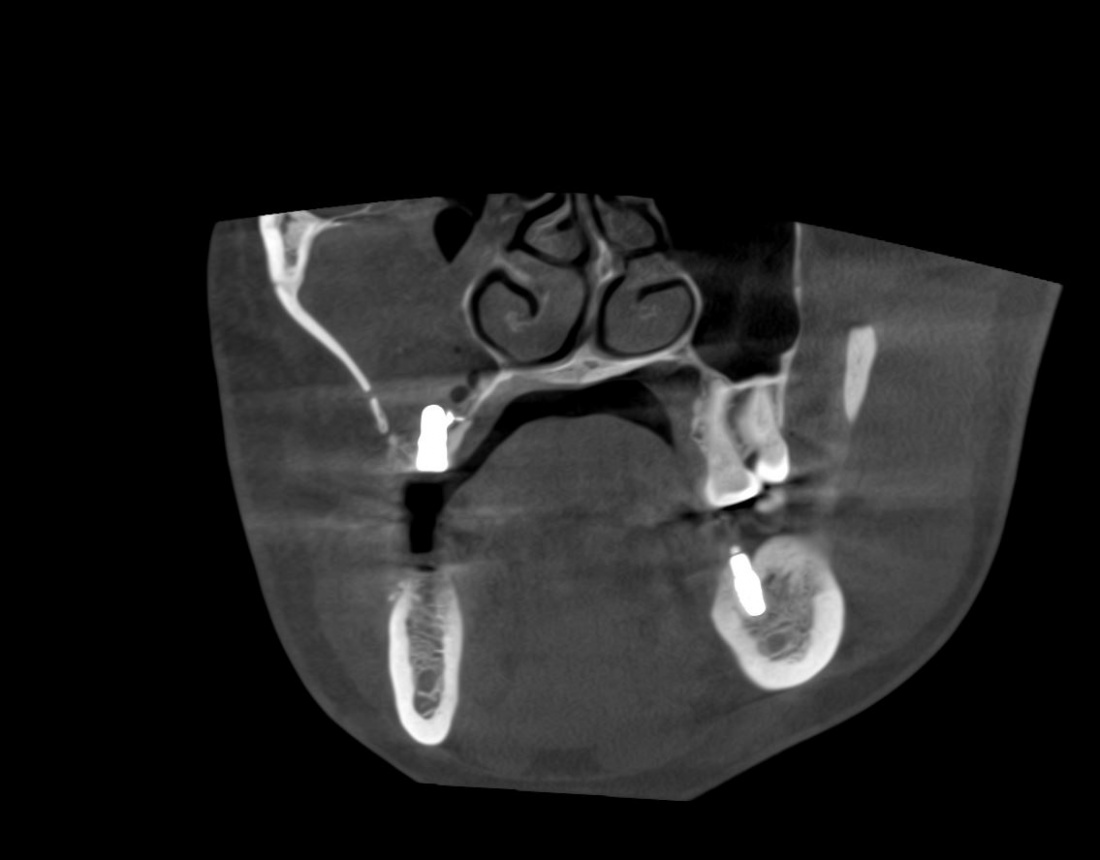

Для этого мы сделали КЛКТ:

И КЛКТ показала нам, что с имплантатами и окружающей костью всё зашибись. Через 12 лет после операции, отсутствия наблюдения, пофигизма в замене временных коронок! Нужны ли тебе еще какие-нибудь доводы в пользу долгосрочной эффективности метода?